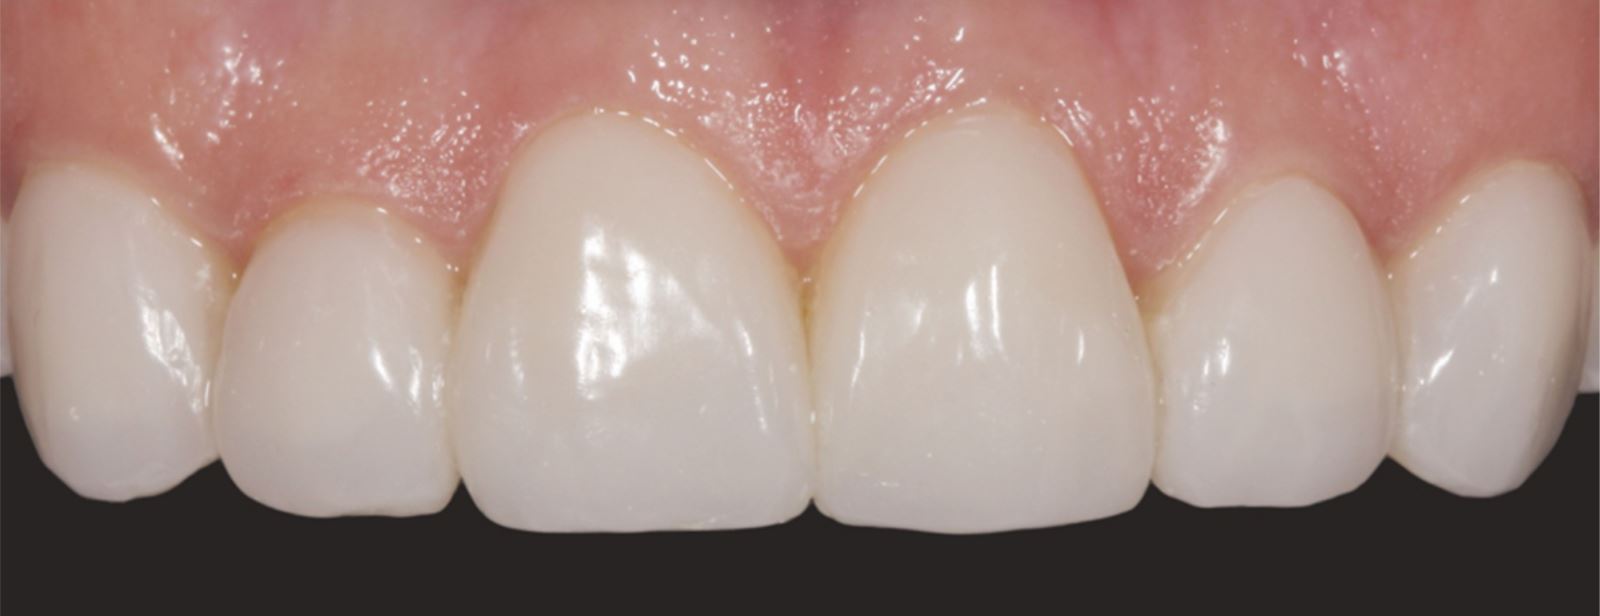

Výsledok cementácie:

Finálna cementácia viedla k stabilnému a esteticky prijateľnému uloženiu faziet.

Výsledok a záverečné zhodnotenie

Tento postup úspešne vyriešil estetické obavy pacientky prekrytím diskolorácie horných frontálnych zubov a dosiahnutím prirodzeného, vyváženého vzhľadu vo vzťahu k dolným frontom. Použitie kompozitných faziet bez preparácie poskytlo konzervatívne, vysoko efektívne riešenie, ktoré rešpektovalo finančné možnosti pacientky a jej požiadavku na minimálne invazívny prístup.